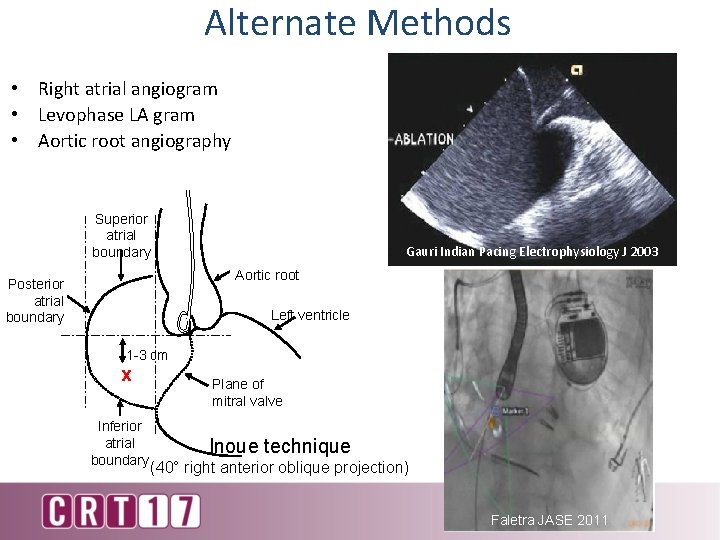

Alternate Methods • Right atrial angiogram • Levophase LA gram • Aortic root angiography Superior atrial boundary Gauri Indian Pacing Electrophysiology J 2003 Aortic root Posterior atrial boundary Left ventricle 1 -3 cm x Inferior atrial boundary Plane of mitral valve Inoue technique (40° right anterior oblique projection) Faletra JASE 2011